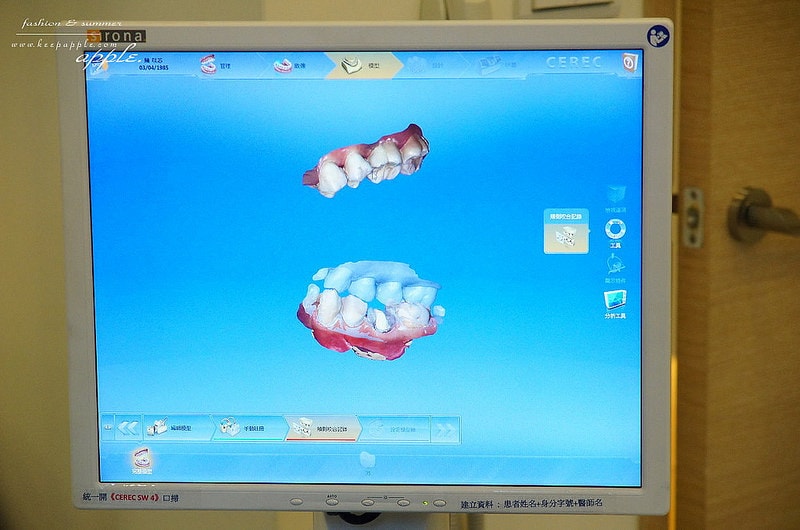

就是用超厲害的數位化口內掃瞄機進行掃描啦!

持續掃描大約三到五分鐘的時間

就可以把整個口腔的牙齒及牙肉組合成3D影像

居然還可以360度翻轉喔!

這台機器真的很厲害,甚至很多大醫院都還沒有引進